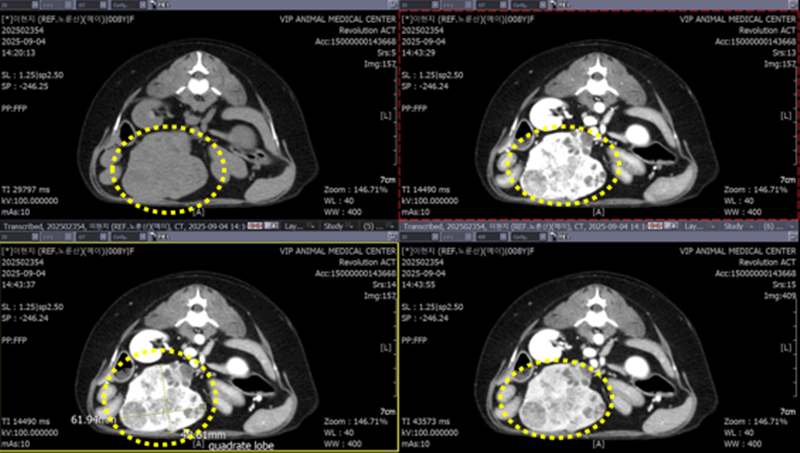

간 네모옆에 돌출된 양상의 비정형 종괴가 확인되었습니다. 크기는 61.9x48.6x78.1mm 로 확인되었습니다.

정자세 그리고 옆에서 장기를 다방만에서 종양의 양상을 확인합니다.

간 우측 내측엽에 문맥 가장자리 조영 Rim enhancement 동반하는 저감쇠 영역도 확인되었습니다. ▼

나나의 경우, 간 주변 림프절이 약간 커져 있는 상태(약 6.1mm)로 확인되었습니다. ▼